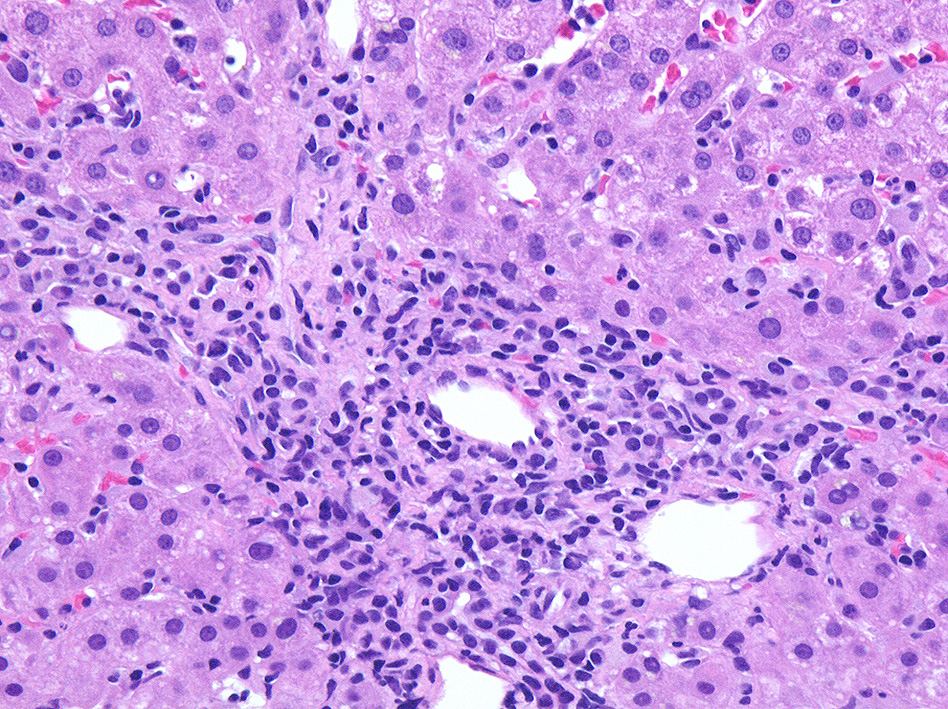

肝臓針生検組織 Virtual Slide--->肝針生検 右クリックで新しいウィンドウ/タブで開くとべんりです。

グリソン鞘, 小葉にリンパ球の浸潤がめだつ。

免疫染色

浸潤リンパ球はCD3+, EBER-ISH+. CD20+細胞はごく少数. CD56, granzymeB陽性リンパ球はほとんど認められない。